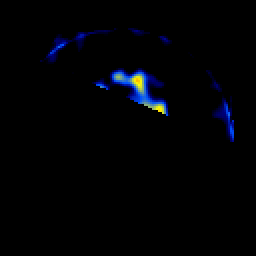

SPECT TL Study #7 -- Slice #52

[Home][Help][Clinical][Tour 1][Tour 2][Tour 3] Slice 52